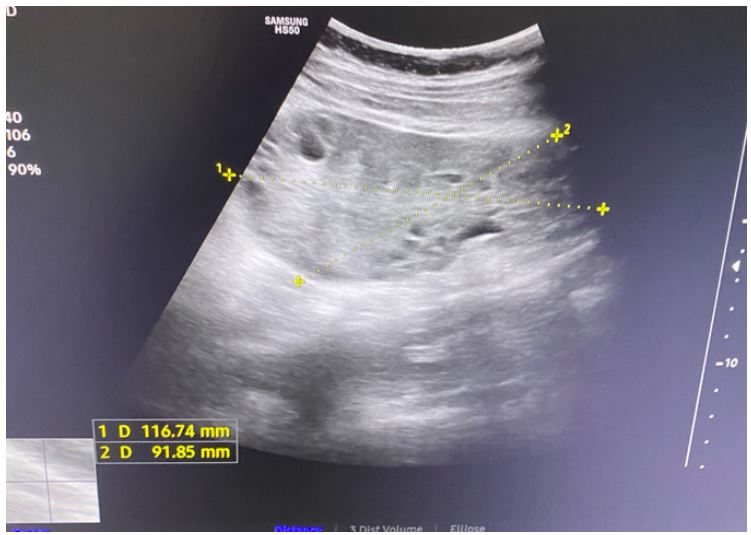

Transabdominal ultrasound identified intrauterine MCMA twin pregnancy. The right ovary measured 14x6.5x9.7 cm with multiple peripherally displaced ovarian follicles resembling a string of pearls (Figures 3 and 4). The left ovary measured 12x7x9.1 cm also with peripheral follicles and stromal oedema (Figure 5). In both ovaries, there was an absent doppler flow. In the region of the right adnexa, there was a collection of free fluid up to 8 mm (Figure 3). Umbilical arterial (UA) Doppler assessment was used in the surveillance of fetal well-being, which showed good fetal condition (Figures 6 and 7).

Figure 4: Abdominal ultrasound: Right ovary with stromal oedema.